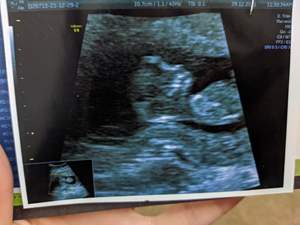

سلام دوستان کسی تعیین جنسیت بلده یا کسیو میشناسه بلد باشه هفته ۱۶ هستم ان تی دادم آنومالی ن هنوز